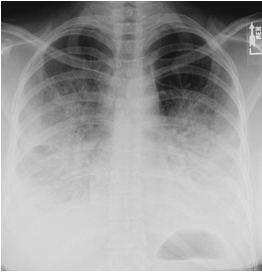

• Chest X-ray shows new bilateral opacities in left upper lobe and right middle lobe; likely infectious process. Increased alveolar infiltrates in the perihilar location and involving lower lobes.

• CT shows no evidence of pulmonary embolism. Heart size normal. Small mediastinal and axillary lymph nodes; none are pathologically enlarged. There are small bilateral pleural effusions with adjacent atelectasis. There are pleural-based airspace opacities bilaterally consistent with acute infectious process.